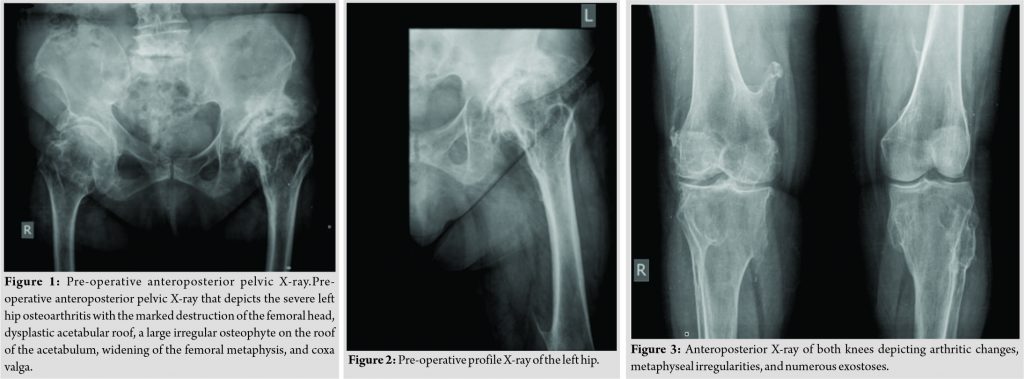

Her radiograph revealed severe hip osteoarthritis with the marked destruction of the femoral head, dysplastic acetabular roof, limited acetabular inclination, a large irregular osteophyte on the roof of the acetabulum, widening of the femoral metaphysis, and coxa valga (Fig. 1, 2, 3). A pre-operative computerized tomography showed the hypoplastic anterior wall, narrow acetabulum, limited bone substrate, the large irregular osteophyte from the femoral head, and the small transverse diameter of the intramedullary canal. The socket, femoral neck, and proximal femur were anteverted (Fig. 4 and 5). Pre-operative planning demonstrated that cemented implants had sufficient structural stability compared to non-modular uncemented under these geometric conditions.